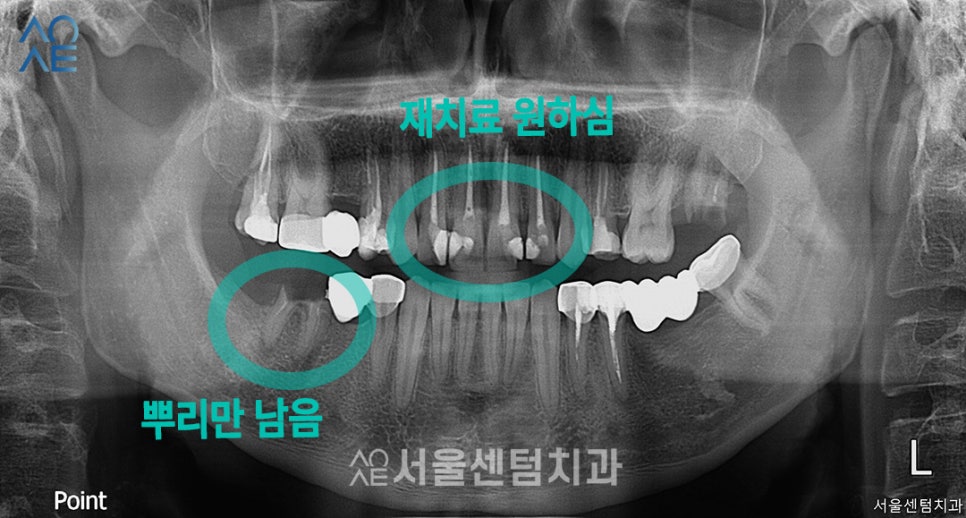

20대임플란트 상담내용

첫 내원 시에는 검진만을 원하셨고

환자분의 요청은 확실했습니다.

제일 먼저, 기존에 치료했던 앞니가

심미적으로 맘에들지 않기 때문에

다시 치료를 하기 원하셨습니다.

20대라는 연령대이기 때문에

잘 보이는 앞니가 신경쓰였던거죠.

또한 치아가 깨져서 뿌리만 남은 부분이 있어서

이부분에 대한 치료를 원하셨습니다.

| 🦷현재 상태 &치료 계획🦷 |

|---|

| (1) 현재 상태🔹 앞니 사이를 때우는 치료를 받았었음🔹 위, 아래에 깨진 치아 있음🔹임플란트가 필요한 부위에 브릿지 보철물 있음 |

| (2) 치료 계획🔹오른쪽 아래에 임플란트 2개 식립🔹앞니 지르코니아 4개 수복 |